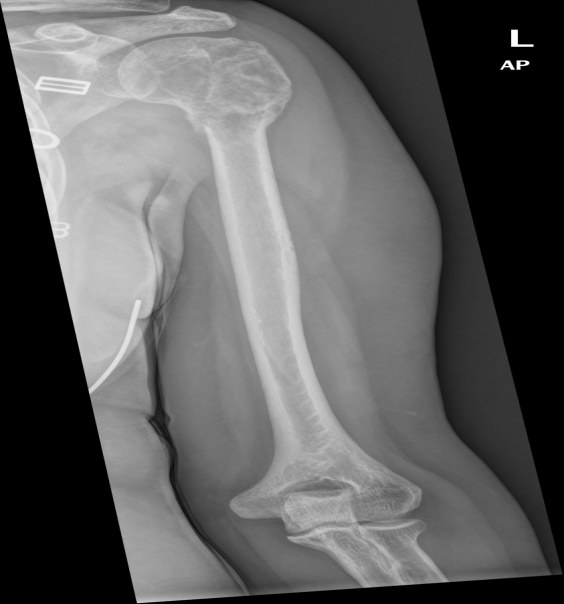

Imaging showed a 5.8 x 5.3 cm lytic expansile lesion in the proximal left humerus. The lesion was also noted on MRI (first photo shown below) and the bone scan. The differential diagnoses included metastasis, giant cell tumor, and possibly myeloma or lymphoma.

The patient also received treatment with Xgeva and has had no medical issues until this recent shoulder and upper arm pain. A new radiograph was obtained and demonstrated increased bony production superimposed on lytic appearance of the left proximal humeral head and slight increased lateral angulation suggestive of a pathologic fracture (third photo shown above).